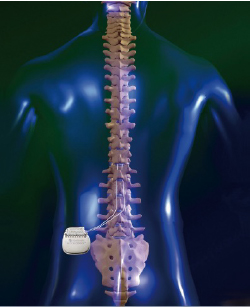

「脊椎脊髄の手術」平林 洌 / 長島 親男 / 戸山 芳昭 / 阿部 俊昭定価: ¥ 20000マーカー少しあり#平林洌 #平林_洌 #長島親男 #長島_親男 #戸山芳昭 #戸山_芳昭 #阿部俊昭 #阿部_俊昭 #本 #自然/医療・薬学・健康